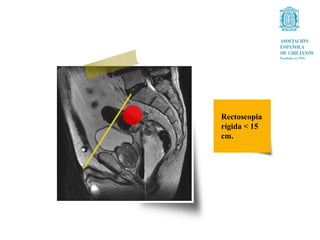

Rectoscopia

rígida < 15

cm.